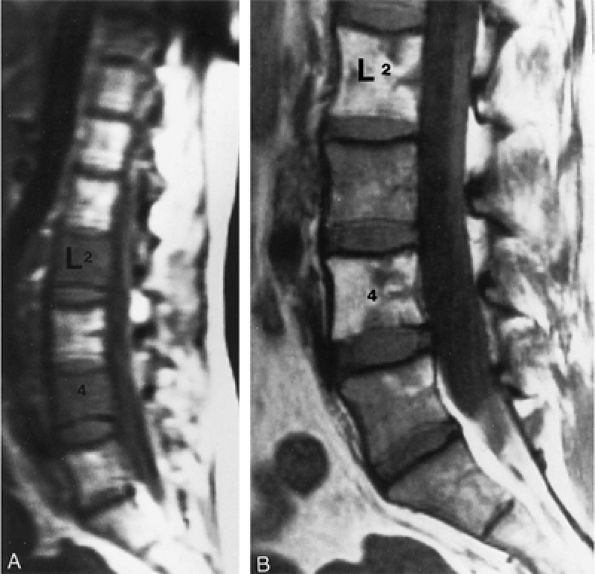

FIGURE 13.16 ● Marrow response to chemotherapy. T1-weighted images of the lumbar spine before chemotherapy (A) and after chemotherapy (B) for metastatic colon carcinoma. Metastatic disease demonstrates low signal intensity at L2 and L4 prior to chemotherapy. High-signal-intensity fatty replacement can be seen after chemotherapy. Adjacent uninvolved vertebral bodies also show a flip-flop in signal intensity as the red marrow is activated.